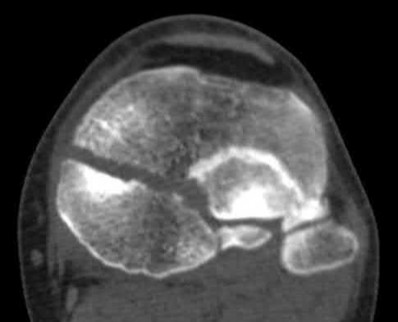

1010) Figures 66a through 66d are the radiographs and CT scans of a 72-year-old woman with osteoporosis who sustained a fall from standing height. She has pain and is unable to bear weight on the right knee. Surgical management is considered. Which of the following best describes the preferred proximal screw fixation construct within a laterally applied buttress plate?

5. 6.5-mm partially threaded cancellous screws Corrent answer: 2

Displaced split depression fractures of the lateral tibial plateau require articular surface elevation, restoration of anatomic plateau width, and sustained elevation of the reduced articular components. This is accomplished by introducing nonlocking lag screws first to compress and narrow the lateral rim thus restoring plateau width. The introduction of locking screws first would disallow compression and accordingly prevent reduction of the lateral rim.

Locking screws are inserted after the lag screws if the bone is osteoporotic to maintain articular elevation. Several biomechanical studies have demonstrated

inferior performance of large implants (6.5-mm screws and 4.5-mm plates) with regard to sustaining joint surface elevation.